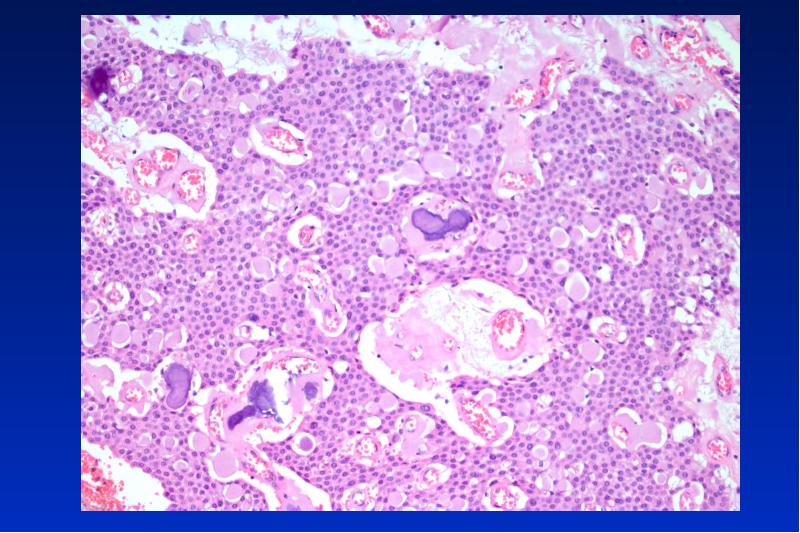

- 38. Ameloblastom solid intraössär/ peripher/unizystisch/ maligen benigner, lokal aggressiv wachsender Tumor

- 45. Unizystisches Ameloblastom 20- 30 Lj unilokuläre Osteolyse 2 histologische